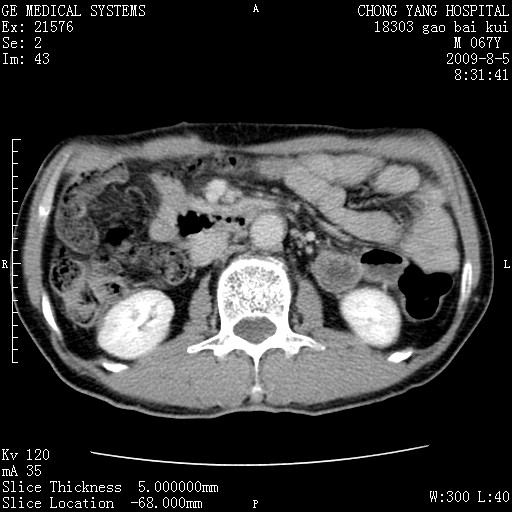

这个也过了,考虑胰腺钩突癌或壶腹癌,不除外胰管粘液乳头瘤伴胰管扩张,肝内胆管积气.

1)考虑胰头癌或壶腹癌并胰管扩张。2)肝外胆管扩张、积气,胆囊影未见;考虑术后改变。3)胃壁增厚?建议必要时行胃镜检查。

虑胰腺钩突癌或壶腹癌,不除外胰管粘液乳头瘤伴胰管扩张,肝内胆管积气.

考虑胰头癌并十二指肠受侵。